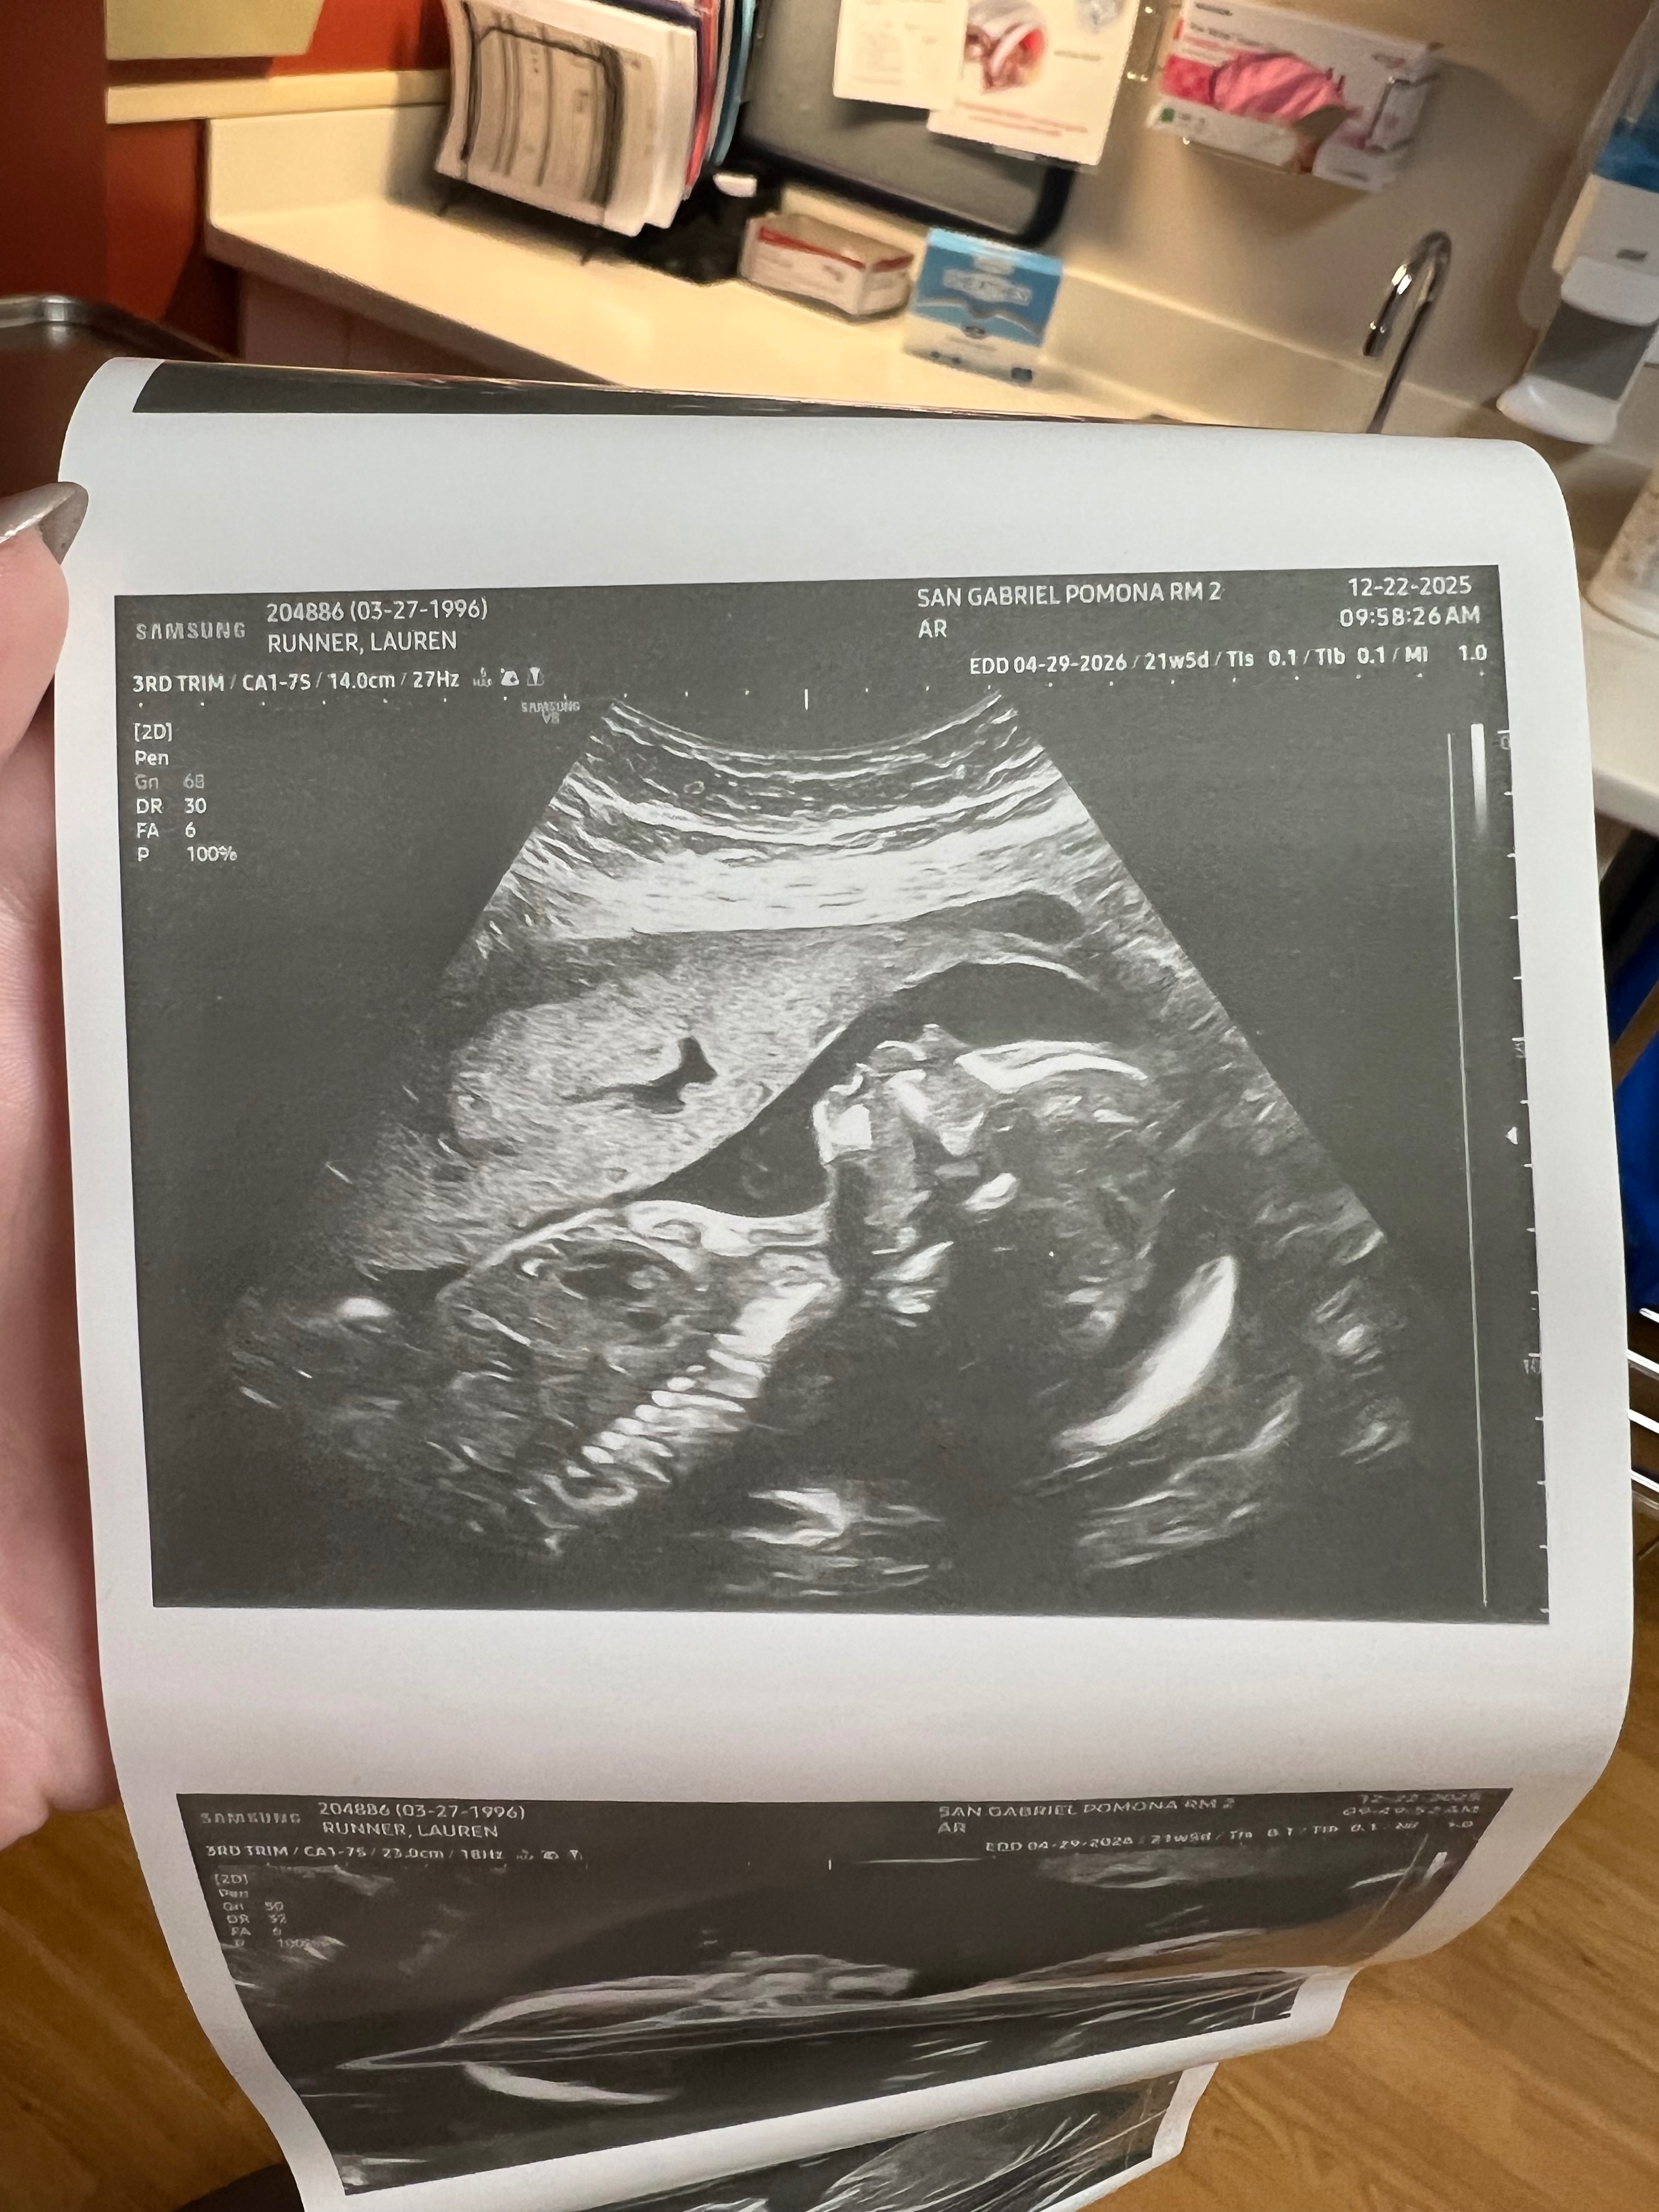

My name is James, and I’m reaching out during one of the most challenging times of my life. About a month ago, I fell off a ladder and suffered a shattered elbow and a fractured skull. Two weeks ago, I had surgery on my elbow, but now I’m back in the hospital due to an infection from the surgery. I need another surgery to try to rid the infection before it gets worse, and I’m facing a long road to recovery. The injuries have left me unable to work for at least the next six months, and I’m currently recovering in the hospital. On top of this, I’m expecting the birth of my son in just three months, which should be a time of joy and excitement, but instead, I’m overwhelmed with worry about how I’ll provide for him and keep up with my bills while I heal.